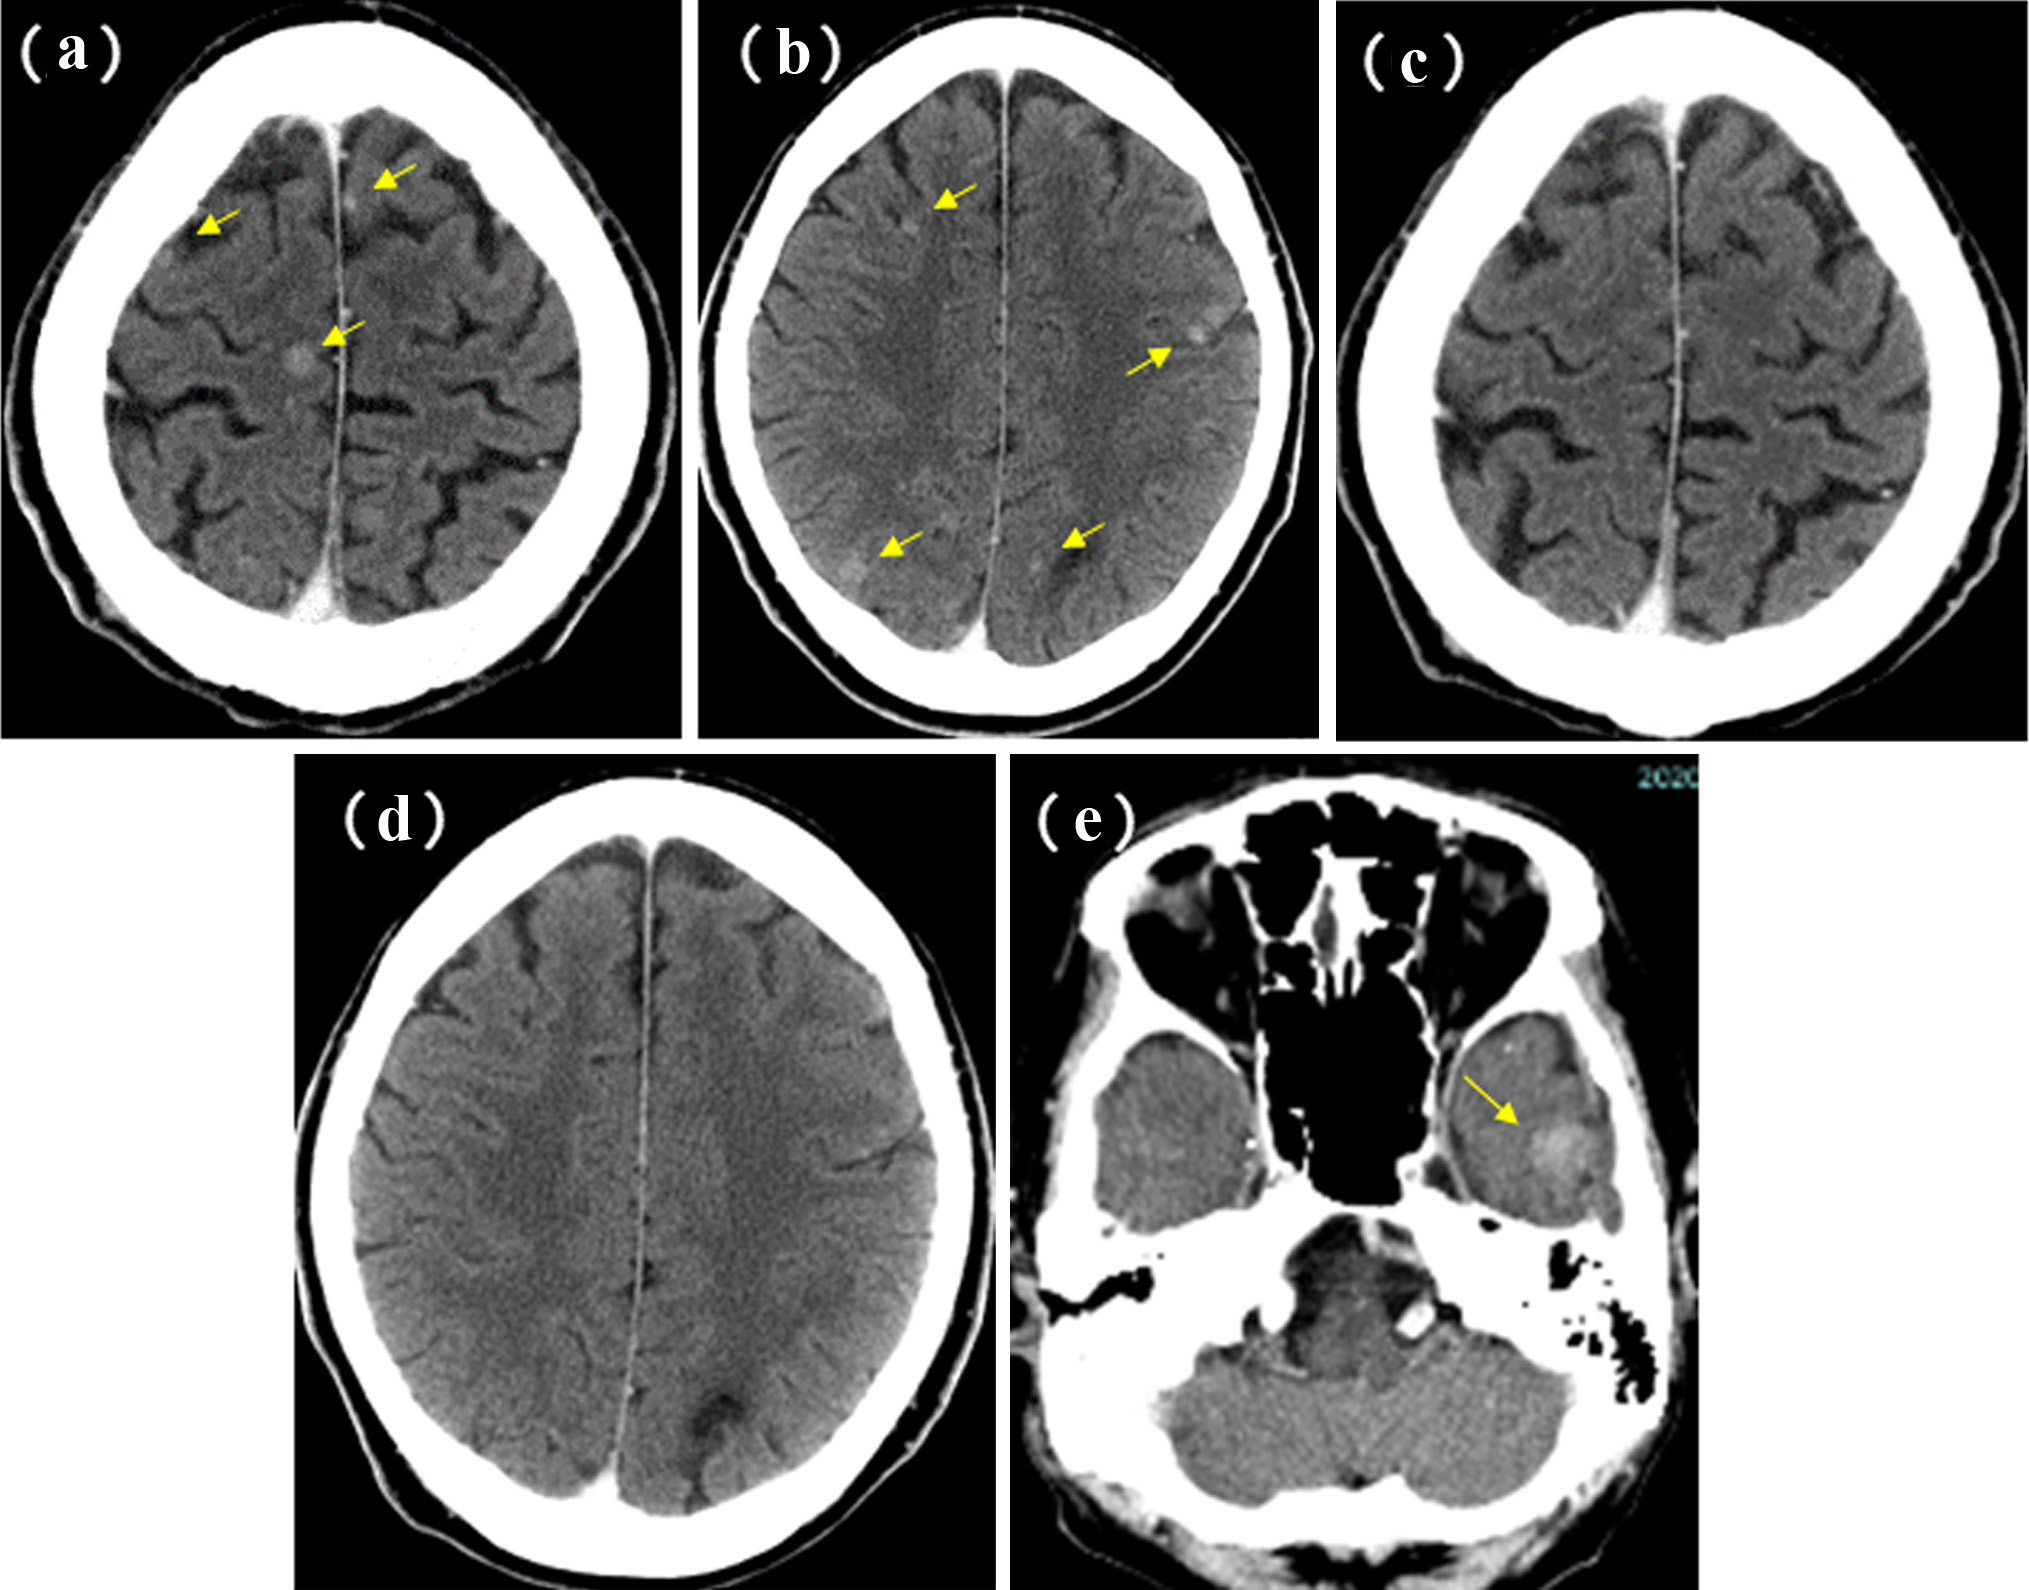

A 58-year-old man was referred to our department because of a tumor shadow in the right middle lung field in April 2010, and presented with a 2-month history of intermittent bloody sputum. He was an ex-smoker with 35 pack-year smoking history, and had no significant medical history except for hypertension. Chest CT showed an 80 × 40 mm sized sub-pleural tumor and multiple intrapulmonary nodules in the right lung. The right hilar, mediastinal and supraclavicular lymph nodes were swollen. He was diagnosed as lung adenocarcinoma by bronchoscopical biopsy from the right B3b (Fig. 6). The clinical stage was c-stage IIIB (cT3N3M0). No EGFR mutation was found in the bronchoscopical specimen by PCR clamp method. Because of the tiny residual specimen, neither ALK nor other mutation could not be examined. The first-line chemotherapy of four courses of induction carboplatin (AUC 6 mg/mL/min, day 1) and pemetrexed (500 mg/m2, day 1) provided PR, but the following two courses of pemetrexed maintenance resulted in progression of the primary tumor, intrapulmonary metastases and multiple mediastinal lymphadenopathies. The second-line of docetaxel (60 mg/m2, day 1) achieved PR temporarily. However, 2 months after the completion of four courses of docetaxel, multiple brain metastases appeared (Fig. 7a, b). Theses metastases successfully disappeared by erlotinib (150 mg/day, every day), which was initiated as the third-line chemotherapy in March 2011 (Fig. 7c, d). Erlotinib was reduced to 100 mg/day in March 2013 because of progressive polymyalgia, which might be retrospectively a prodromal symptom of polycythemia vera. We tried stopping erlotinib in March 2020, because no recurrence had been found for 9 years after the initiation of erlotinib. However, 3 months after the discontinuation of erlotinib, a solitary metastasis appeared in the left temporal lobe (Fig. 7e). He received GKR at another hospital in July 2020, and then resumed erlotinib in August 2020. Hydroxycarbamide (500 mg/day, 3 days/week) was started by hematologists in October 2020 for polycythemia vera harboring JAK2V617 mutation, when peripheral leukocyte count was continuously over 70,000 cells/µL. Thereafter, he continued combination of hydroxycarbamide and erlotinib, and no recurrence of lung cancer had been found in October 2022, 11 years and 8 months after the start of erlotinib. He experienced grade 4 of retroperitoneal hemorrhage in January 2020, grade 3 of intramuscular hematoma in the left femoral muscle in May 2015, grade 2 of skin hyperpigmentation, paronychia and multiple compression fractures.

![]() Click for large image | Figure 7. Brain metastases of case 2. Before (in March 2011) (a, b) and 3 months after (in June 2011) (c, d) the initiation of erlotinib monotherapy. (e) Appearance of the left temporal metastasis 3 months after the discontinuation of erlotinib. Yellow arrows show the brain metastases. |